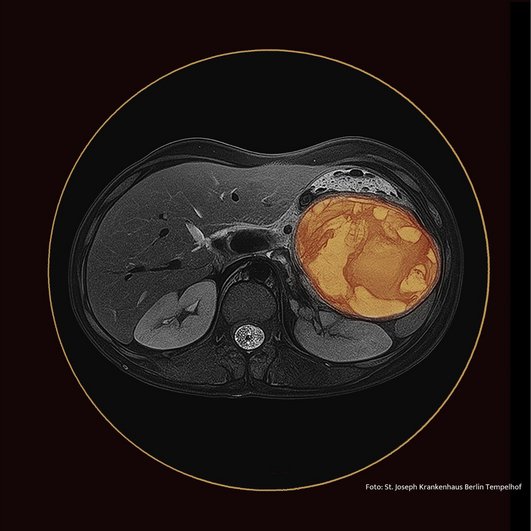

Die unser heutiges Infektoskop begleitende - mit allen Mitteln der Bildbearbeitung manipulierte - MRT ihres Abdomens zeigt eine ovaläre Raumforderung im linken Mittelbauch mit einem transversalen Durchmesser von 10 x 8 cm. Diese Läsion führt zu einer Verlagerung der Cauda des Pankreas nach kaudal. In der T2w-Sequenz ist sie signalinhomogen mit signalhyperintensen zentralen Anteilen und Septen. In der diffusionsgewichteten Bildgebung ist diese vornehmlich zentral diffusionsgestört. Wir zeigen die Bilder Herrn Tröger, dem Chefarzt für Gastroenterologie. Sein spontanes Urteil: „Das ist ein Frantz Tumor.“ Der Chefarzt der Radiologie, Herr Trübenbach, hat viel nachgedacht und auch er kommt zu dem Schluss, dass das Bild mit der Verdachtsdiagnose Frantz Tumor sehr gut vereinbar sei. Seine Differentialdiagnose „Abszess“ schätzt er als weniger wahrscheinlich ein. Beide werden recht behalten, aber ihr Verdacht wird die Geschichte nicht in ihrer Vollständigkeit umfassen, sonst wäre dies hier nur ein „Gastroskop“ und nicht auch ein „Infektoskop“.